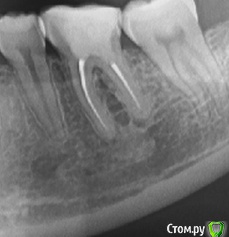

Снимок зуба 2 года назад

post-50922-0-21139200-1493654890_thumb.jpg

Нижний зуб 6-ка, депульпирован около 11 лет назад. Два года назад обновляли пломбу на нем.